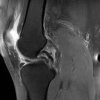

Knee – Bucket Handle Tear & ACL Tear

Case History 32 Year old female Felt a pop in the knee when doing box jumps. Developed knee pain with slow swelling. Improved a couple of weeks later. 5 Months later while doing weighted lunges, knee popped again. Improved again but residual pain persisted. Continued to do cross fit. Referred to MSK Physio by GP. Examination Mild end range flexion [...] Read more